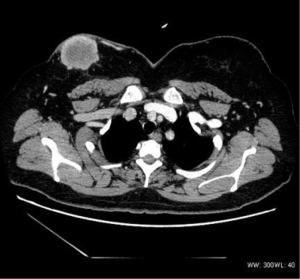

The density was uneven in the five mediastinum tumor cases, which included one case with patchy vcalcification. Four cases had uneven enhancement after the dynamic enhanced scan, and one case exhibited obvious enhancement. All five cases had lymph node metastasis. Furthermore, one case had multiple metastases of the bilateral lungs, subpleural, liver, and bone (Figure 3), and one case had involvement of the left and right pulmonary arteries and superior vena cava. In two cases the metastasis involved the pericardium and mediastinum pleura.